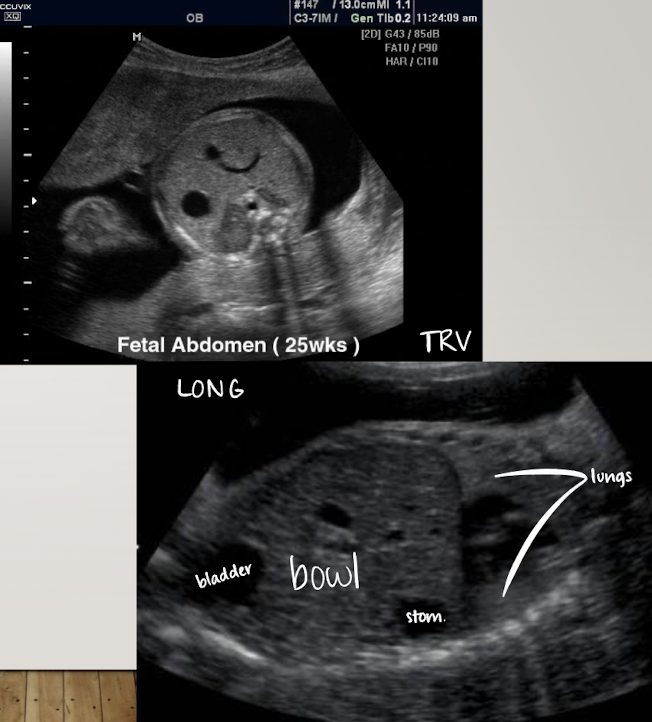

stomach

in LUQ

seen by 16w

amniotic, fluid-filled structure

if no fluid seen, evaluate 20-30 minutes

used as a marker for taking AC measurement

evaluating stomach

scanned in TRV plane (short axis)

anechoic (fluid-filled)

if stomach is empty, move on and come back later or have patient come back another day

can also image stomach and bladder together in LONG

bladder

distended bladder should be seen by 13wks

empties and fills at least once every 30 minutes

if not identified on exam; exam must be repeated within 24 hours

empty bladder is an indication of abnormality

SONO:

document in LONG and TRV